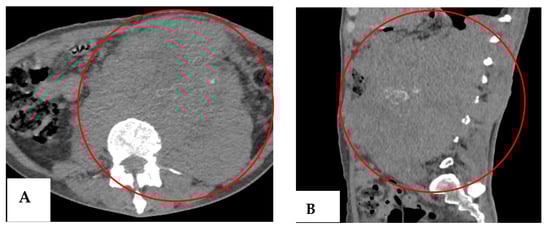

Our patient remained under follow-up by the medical oncology department, so new tumor markers were ordered in July 2023, with elevated LDH (1354 IU/L) and β-hCG (93.56 mIU/mL) (Table 2). Additionally, a CT scan was required, which showed an increase in the size of the cluster (Figure 5), corroborating an unsuccessful therapy, considered progressive disease according to RECIST (Response Evaluation Criteria in Solid Tumors) criteria.

Figure 5. Follow-up CT scan (July 2023). (A) Axial section showing an enlarged mass with a larger necrotic component and anterior extension (red circle). (B) Coronal section showing the craniocaudal extension of the mass from T10 to S1 (red oval).